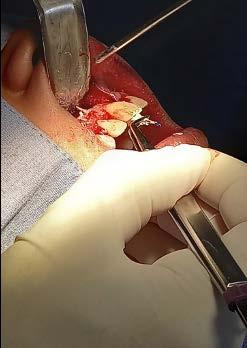

Reporte de caso clínico

Paciente masculino de 10 años, se presenta a la consulta en la clínica Gnathos, la mamá reporta desagrado en la estética dental y facial del paciente. En la exploración clínica se observa mordida profunda, amplio número de piezas dentales con caries, fracturas dentales, mala higiene y encías inflamadas. presenta clase II división 2, se le indicaron estudios complementarios para diagnóstico asertivo, modelos de estudio,

Después de haber realizado el diagnóstico y plan de tratamiento, se remitió a extracción de restos

Figura 3. Primer aparto SN1 con almohadillas vestibulares. A. VF con aparato, B. VL derecha C. VL izquierda. D. SN1, vista oclusal (VO). Después de 7 meses del tratamiento se observa los avances obtenidos por el aparato y los ajustes del mismo los cuales observamos en las figuras: E. VO del SN1 7mm de crecimiento transversal, F. VF con aparato, 3G. VL derecha, H. VL izquierda.

radiculares de O.D. 73 y 83 y rehabilitación oral completa de O.D. 54, 63,65 y 75. Se procedió a colocar aparatos ortopédicos para corrección de la maloclusión en enero del 2022.

El tratamiento inicio con AOF, SN1 con Equiplan adicionando almohadillas vestibulares en el maxilar para despresurizar la acción de la musculatura labial. La indicación de uso fue utilizarlo de forma continua solo retirándose para comer e higienizar, activar del tornillo tanto superior como inferior una vez a la semana, y se realizaron revisiones mensuales en la clínica para valorar avances, llevar

a cabo activaciones, ajustes del aparato e indicaciones. Como se observa en la Figura 3.